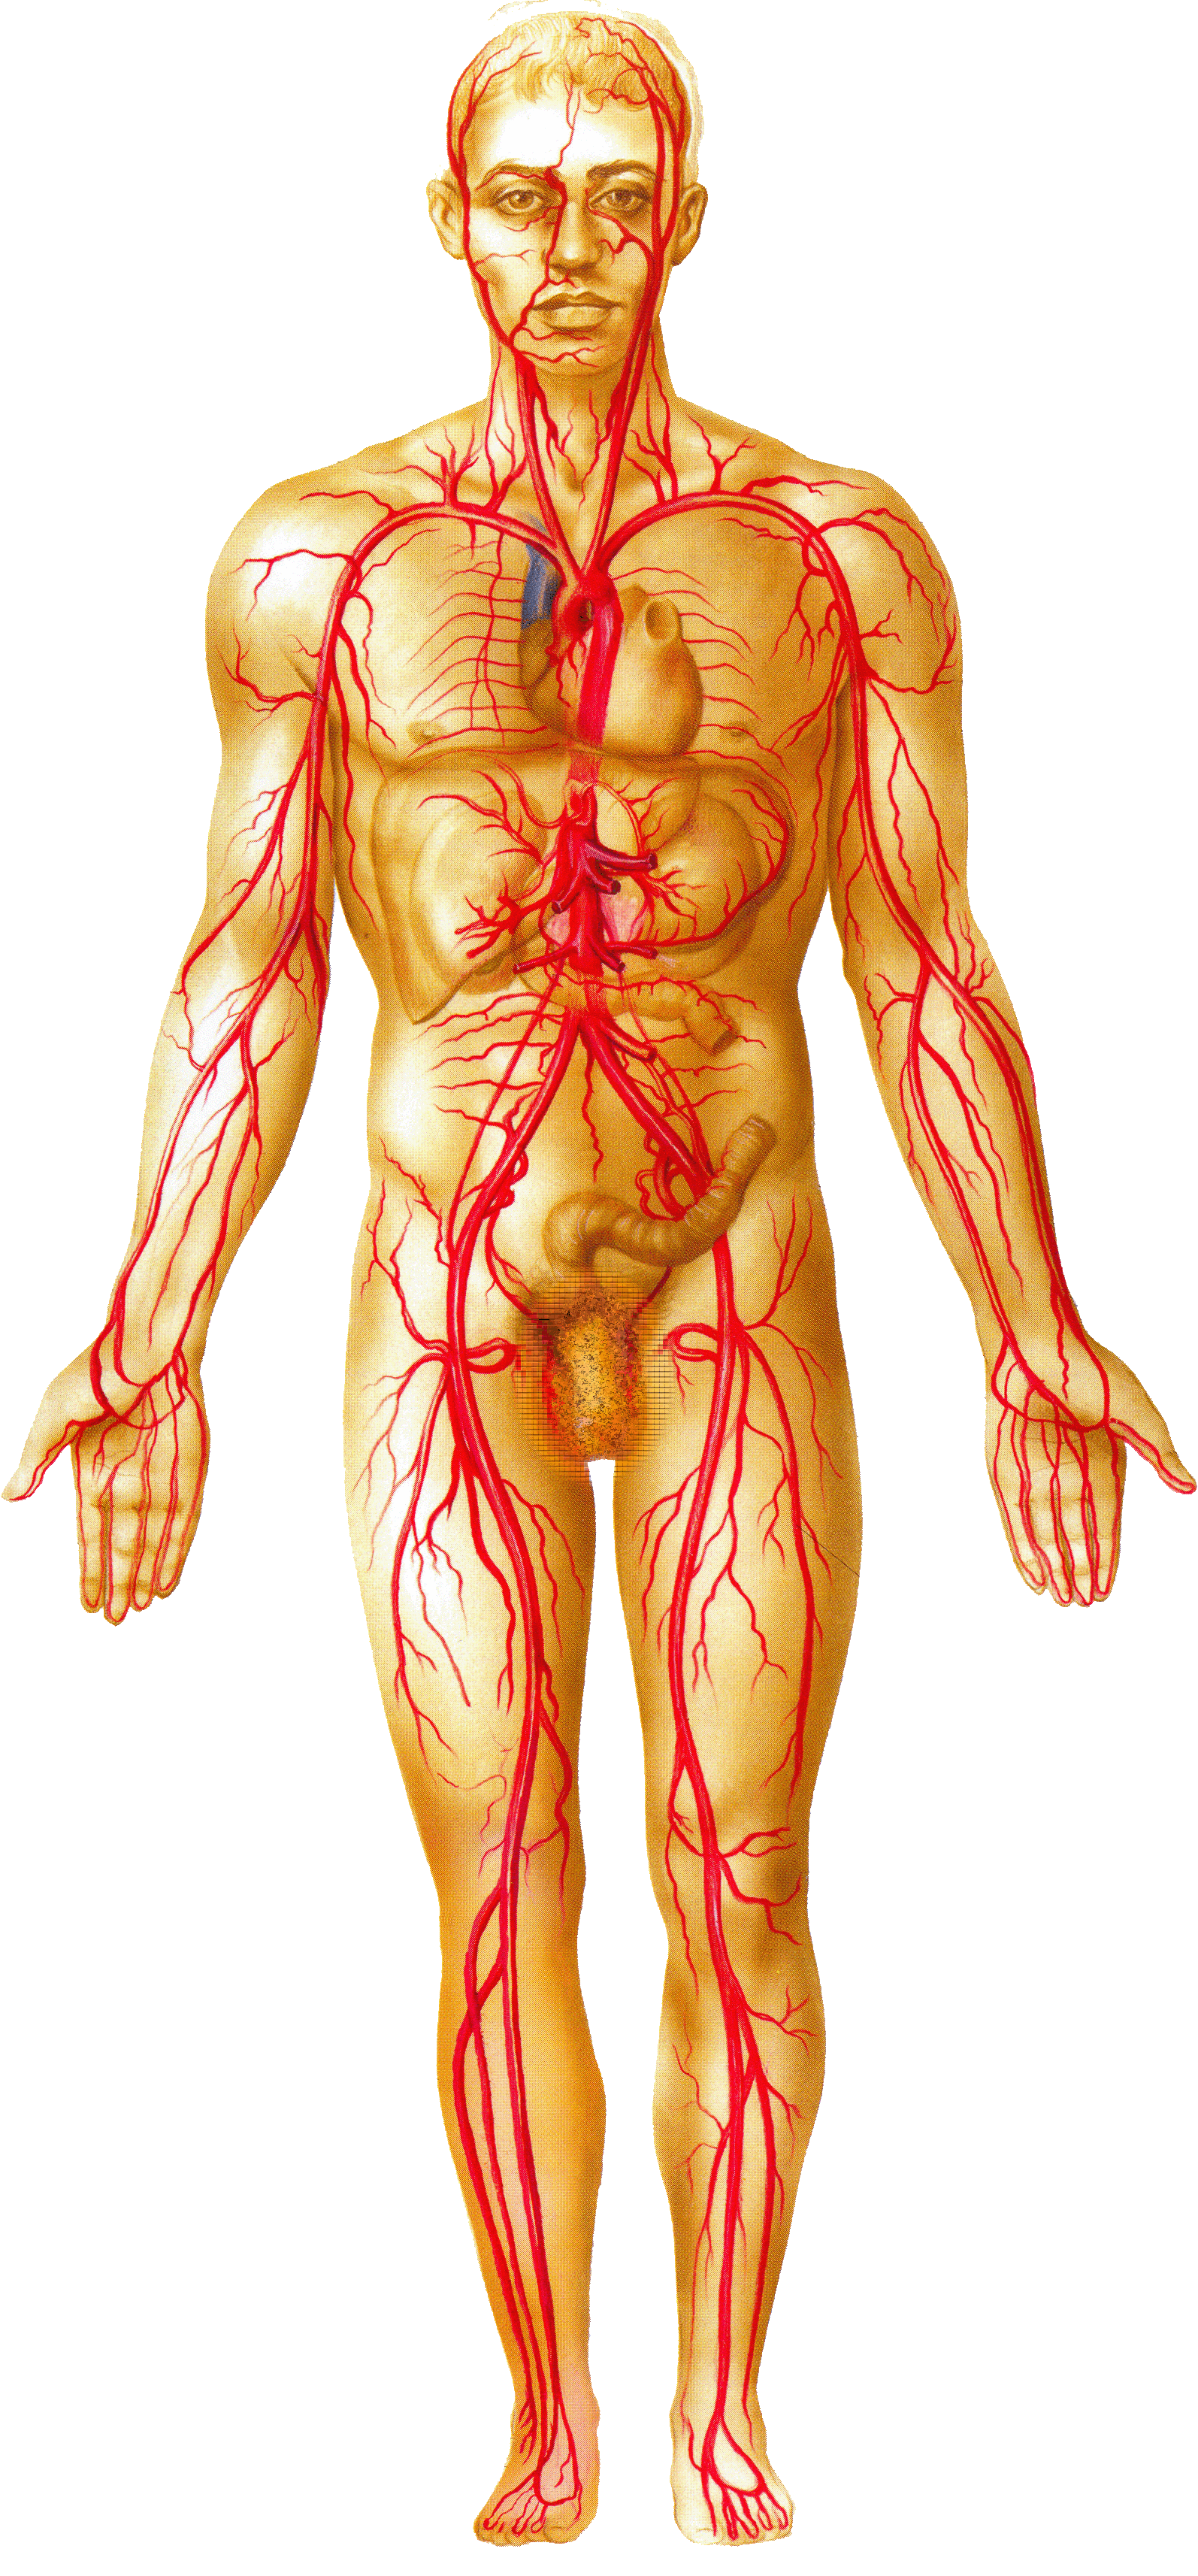

Кровеносная система человека: структура и функции

Раздел: Идеи и советы